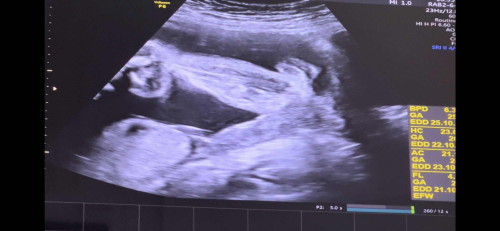

คุณหมอบอกว่าเป็นกลีบเด็ก ญ คิดว่าชัวร์ไหมคะแม่ๆ จะไม่ใช่ไข่เด็ก ช โผล่มาใช่มั้ยคะ😂😂 น้อง26weeksค่ะ